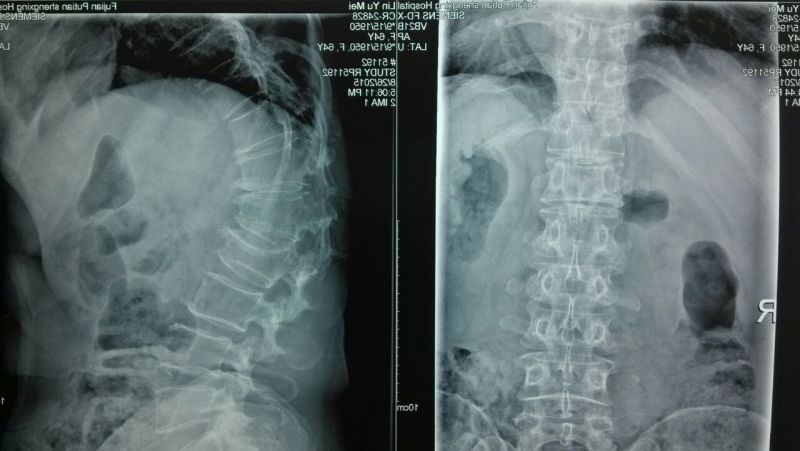

術(shù)前DR片